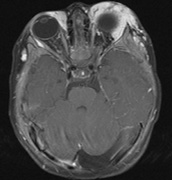

The incidence of optic pathway gliomas in NF1 is difficult to estimate, as the majority are asymptomatic and do not affect vision. In NF1, radiographic evidence of an optic nerve glioma occurs in 15% of patients.64,65 Most tumors are neither suspected historically nor detected by ophthalmic examination.65 Even when optic nerve gliomas become clinically detectable, visual function often remains stable in the absence of any intervention.66,67 Thus routine computed tomography (CT) imaging, even in patients with a known optic nerve glioma, is controversial. The potential risks of repeated radiation exposure in a child with a tumor-suppressor gene defect is a consideration. MRI studies are more revealing than CT but may require sedation or anesthetic and are costly. An MRI is often recommended at the time of diagnosis, but in most cases routine “follow-up” MRIs are unnecessary. Annual ophthalmic clinical examination for relative afferent pupillary defect (RAPD), visual acuity, visual fields, color vision, and funduscopy is usually all that is required, as no therapeutic action is likely to be taken unless there is significant and progressive visual involvement. Optic nerve gliomas may involve the optic chiasm and be associated with endocrine disorders or nystagmus.68–70 Surgical excision of chiasmal gliomas (Fig. 6) carries a high risk of visual loss. Invasion of the hypothalamus or the third ventricle carries a poor prognosis, with greater than 50% 15-year mortality rate.71 One review of radiation treatment for chiasmal gliomas collated data from small case series and found no significant long-term improvement in visual function, progression, or mortality with radiation treatment.71 Other reports suggest that radiation doses over 4500cGy improve symptoms and slow progression of chiasmal gliomas over several years.72 Adequate tumor coverage by radiotherapy results in irradiation of normal brain and nearly all children need hormone replacement.73 Chemotherapy is an alternative.74,75